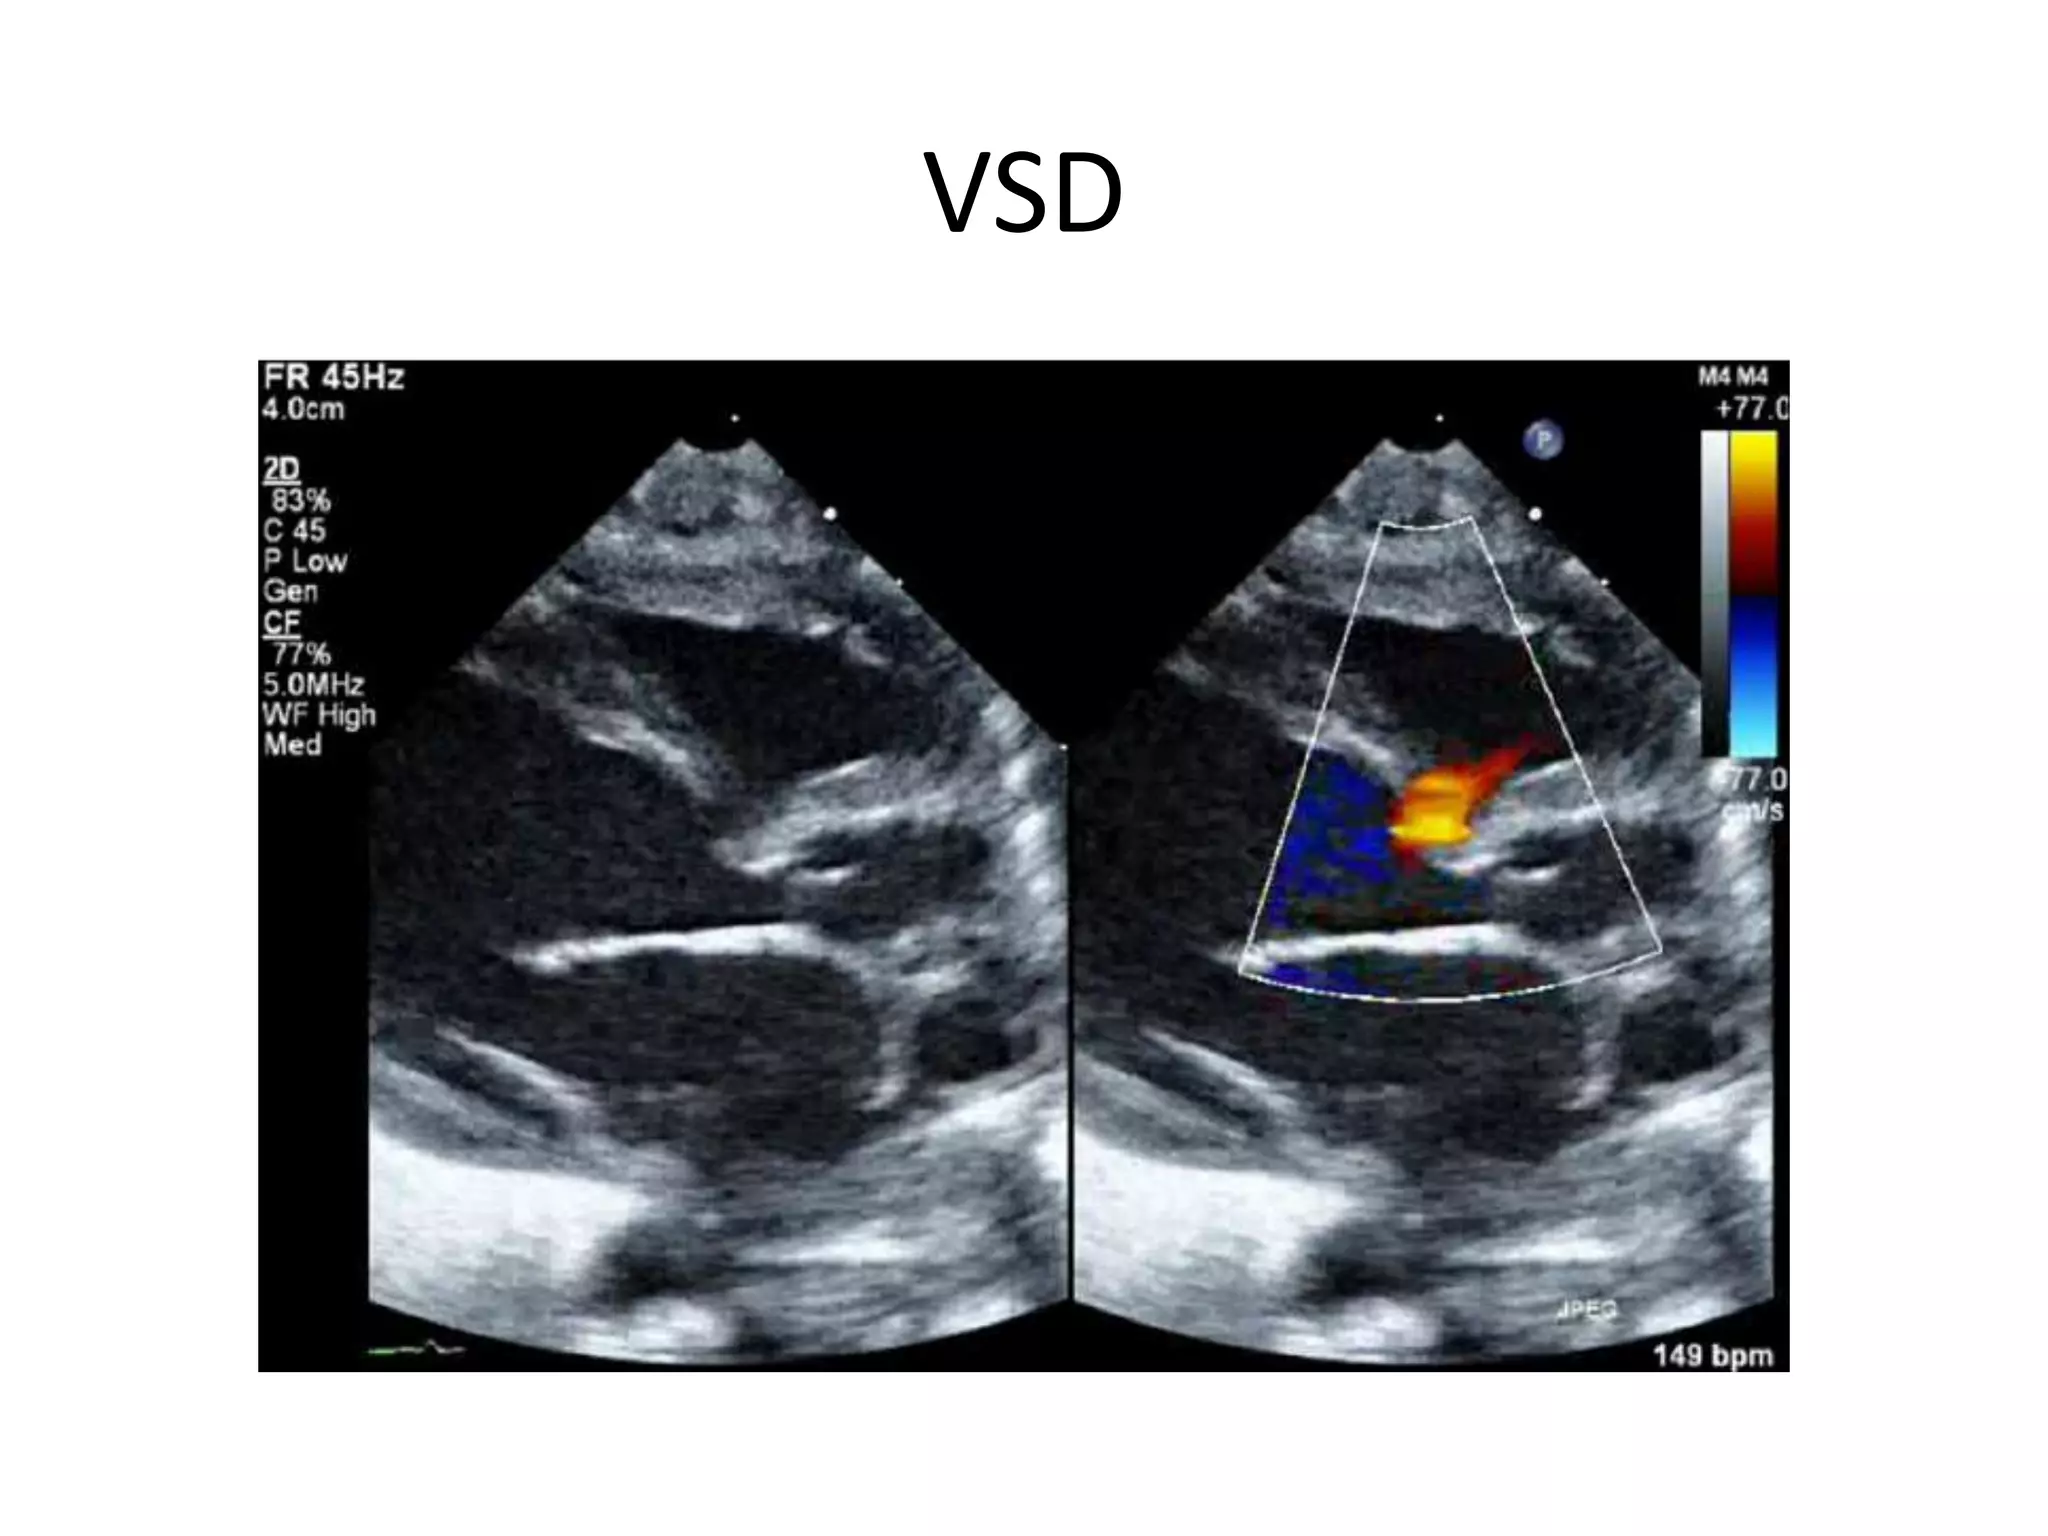

VSD